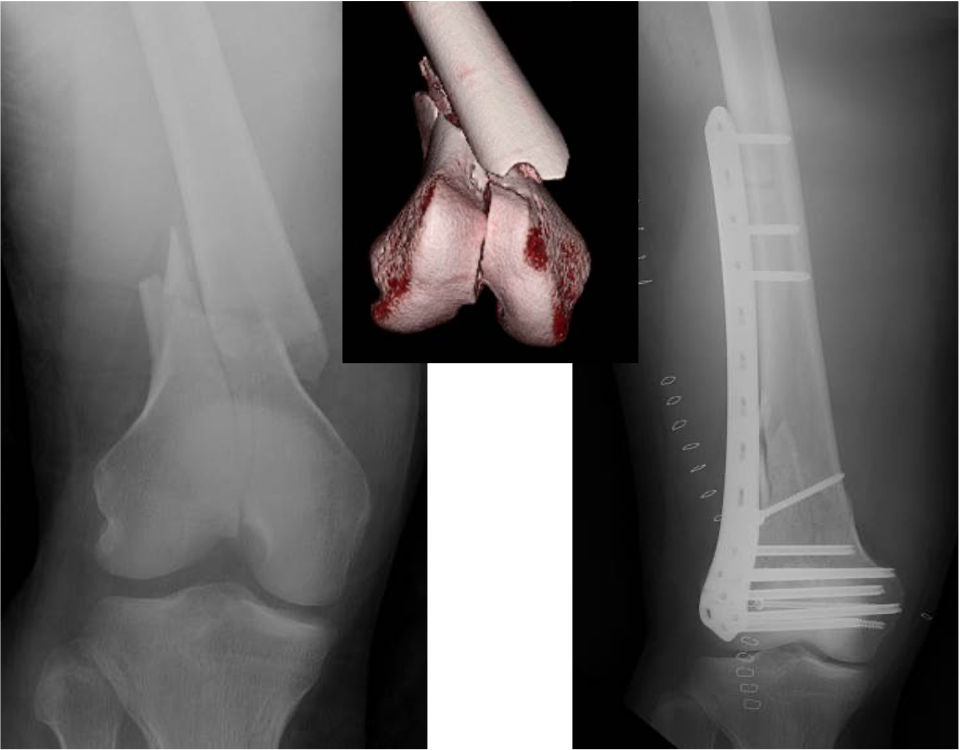

関節を含む骨折は、機能障害を起こしやすく、正確に関節を再建する必要があり、早期リハビリ、機能改善にはとても重要です。

大腿骨遠位端骨折に対する骨接合術

足関節脱臼骨折に対する骨接合術